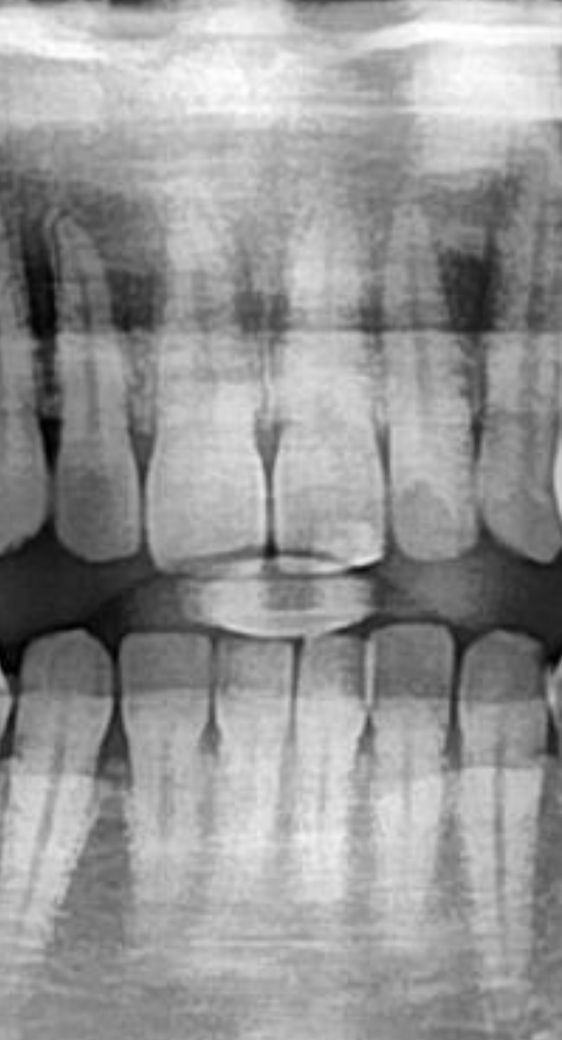

딱딱한거 깨물어서 위쪽 앞니 두개가 쑤시네요

혹시나 싶어서 사진을 한번 올려봅니다

최근 인터넷 검색해보니 뿌리에 크랙이 생길수도 있다고 들어서 걱정되네요

• 1번 째 사진

사진상으로는 문제가 보이진 않습니다.

증상이 계속나타나면 크랙도 의심해볼 수 있습니다